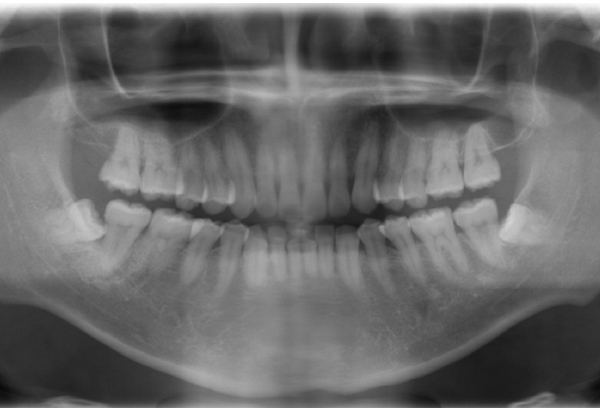

パノラマレントゲン撮影

本格的に治療を進める場合は、精密検査・診断(11,000円税込)を行います。

精密検査では

- パノラマレントゲン

- 口腔内写真

- 口腔内スキャナー「SIRIOS」

による3Dスキャンを行い、歯並びや噛み合わせの状態を詳しく分析します。

取得した検査データをもとに、お一人おひとりに適した治療計画をご提案いたします。